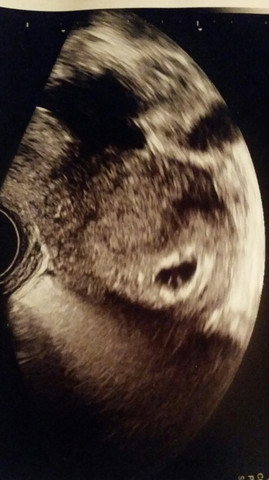

Der Dottersack ist die erste embryonale Struktur, die man im Ultraschall in der Frühschwangerschaft erkennen kann 2 Das Vorhandensein eines Dottersacks soll dokumentiert werden, der Durchmesser soll gemessen und ebenfalls dokumentiert werden 3 Es ist darauf zu achten, dass Dottersack und Scheitel Ultraschall 60 kein Embryo sichtbar. Schwangerschaftswoche nachweisbar sein, der Dottersack nach 5,5 Wochen und ein embryonaler Pol nach 6 Wochen Um diese Strukturen sehen zu können, muss der ßHCGSpiegel über 1500 mU/ml liegen Typische Hinweise auf eine ektope Schwangerschaft sind freie Flüssigkeit im Beckenraum, das Fehlen einer Fruchtblase im Uterus sowie eine zystische. Ein Ultraschallbild vom 5 der 6 Schwangerschaftswoche (55) Hier ist der Dottersack nun sehr deutlich zu sehen (man sieht hier auch, wie wichtig die Qualität der Ultraschallgeräts sein kann Der Dottersack wurde hier vermessen und hat einen Durchmesser von 3 Millimetern Der Embryo ist auf diesem Bild noch nicht davon abgrenzbar.

Ein Ultraschallbild vom 5 der 6 Schwangerschaftswoche (55) Hier ist der Dottersack nun sehr deutlich zu sehen (man sieht hier auch, wie wichtig die Qualität der Ultraschallgeräts sein kann Der Dottersack wurde hier vermessen und hat einen Durchmesser von 3 Millimetern Der Embryo ist auf diesem Bild noch nicht davon abgrenzbar. Bild 104 7SSW, deutlich sichtbat der 105 mm große Embryo, unterhalb der Dottersack Bild 105 In der Fruchthöhle der 12 mm lange Embryo, Anfang 8 SSW Die Frucht ist vom Amnion, der späteren Fruchtblase umgeben Bild 106 Noch deutlicher sichtbar das Amnion und ein mm langer Embryo in der 9 SSW. Eine Ultraschallkontrolle nach nur drei en ist praktisch gar nicht in der Lage, eine Aussage zum Verlauf zu machen, wenn sich nicht bedeutend etwas geändert hat Der Dottersack und die Plazenta dagegen schon (da von einem anderenBereich entwickelt ) Oder es ist ein gaaanz früher Missed Abortoder oderviele Ärzte sagen gerne es sei ein Windei, damit man nicht soooo Trauert wenn man denkt es war nur ein Leeres Ei , statt einem Frühen Abort.